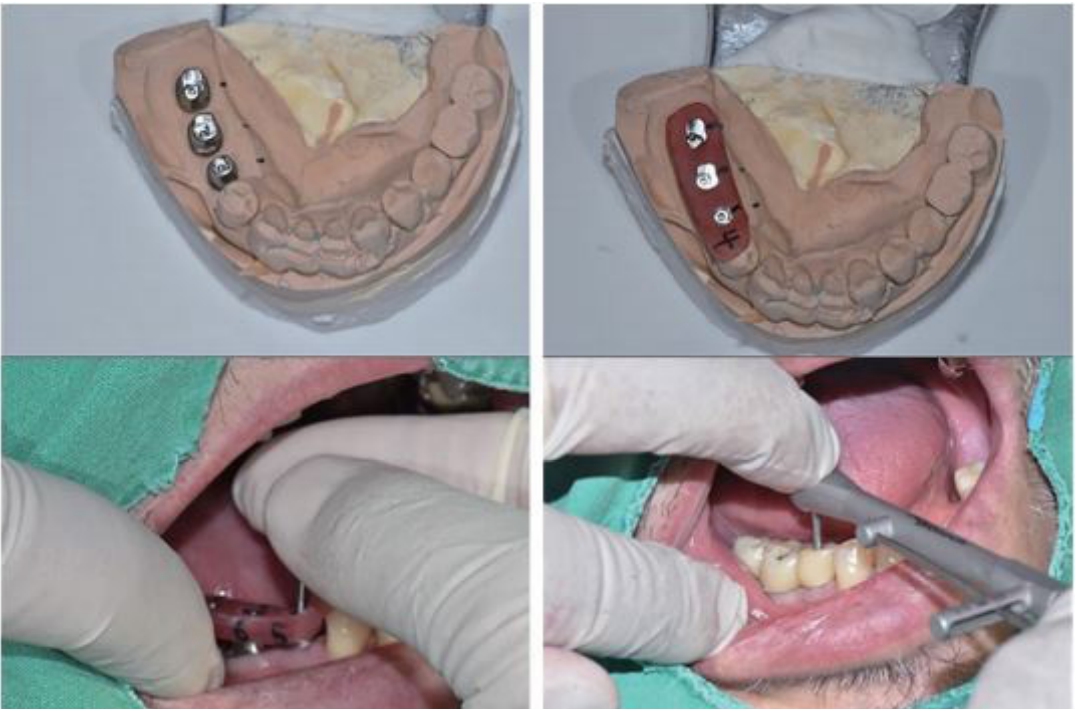

최근 digital techniology 의해 임플란트 보철물의 제작이 점점 증가되고 있지만 아직도 대부분의 임플란트 보철물은 인상채득에 의해서 모형위의 제작이 많은 것이 현실이다. 또한 최근 심미적이고 치주적인 관점에서 기성 abutment 에 비해 custom abutment가 많이 이용되고 있는 현실이다. 여기에서는 custom abutment를 위한 Fixture level 인상 채득 후 완성된 보철물의 장착을 위한 술식을 설명하고자 한다. 완성된 임플란트 보철물은 custom abutment를 이용하는 경우에, Abutment location Jig를 이용하여 구강 내에 Abutment를 장착한 후 보철물을 Bite stick을 이용해서 완전하게 seating시킨 후에 우선 인접치아와의 접촉정도 (자연치아 crown일 때보다 약간 tight한 것이 좋음)를 확인한 후 그리고 방사선 사진에서 fixture에 abutment가 잘 맞게 끼워졌는지 그리고 abutment와 crown간의 적합상태를 확인해야 한다(그림 15). 그 이후 교합관계를 확인 후 필 요하면 교합조정을 해야한다.

2) Custom abutments 이용한 임플란트 보철물의 장착 순서

임플란트 보철물은 (표 4)와 같이 여러 단계를 순서대로 진행하게 된다.

(l) Abutment screw의 tightening

Torque wrench를 이용하여 Screw를 조여줄 때 crown을 낀 상태에서 tightening 하는 것이 좋으며, 30N으로 Screw를 tightening 해 준 후 약 8분 후에 다시 한번 30N으로 screw를 조여주는 것이 좋다. 이는 첫번째 조여진 fixtu re 내면과 screw에 발생된 stress가 relieve 되면서 약간 느슨해질 수 있기 때문이다. 이러한 과정이 screw의 풀림현상 을 줄여주는 데에 도움이 된다(그림 16)